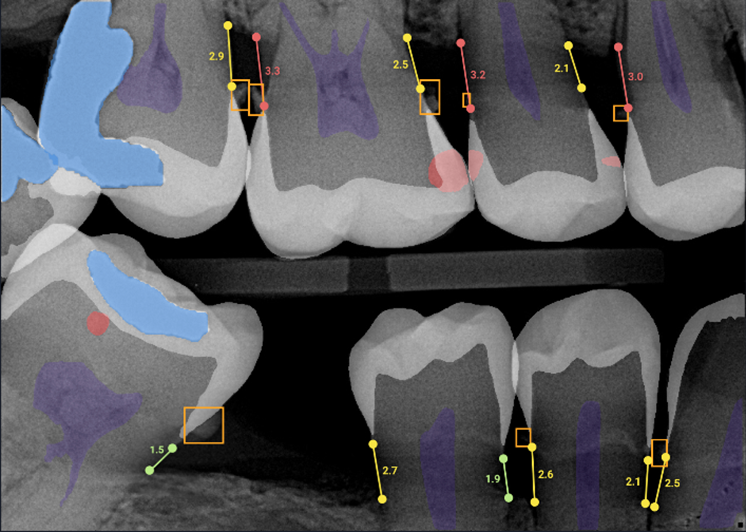

Overjet Xray

X-Ray

Overjet Withoverjetxray

X-Ray with OVERJET

Through years of training, our dentists are experts in reading imaging results, able to see decay, cavities and more on your X-rays. For the lay person, these results are often much more difficult to interpret, even when the dentist is pointing out what he or she is seeing. OVERJET technology analyzes the X-ray images similar to how the dentist would, then overlays that image with colored highlighting and measurements to illuminate any diseases, conditions and more. Essentially, this allows our patients to see what the dentist sees!